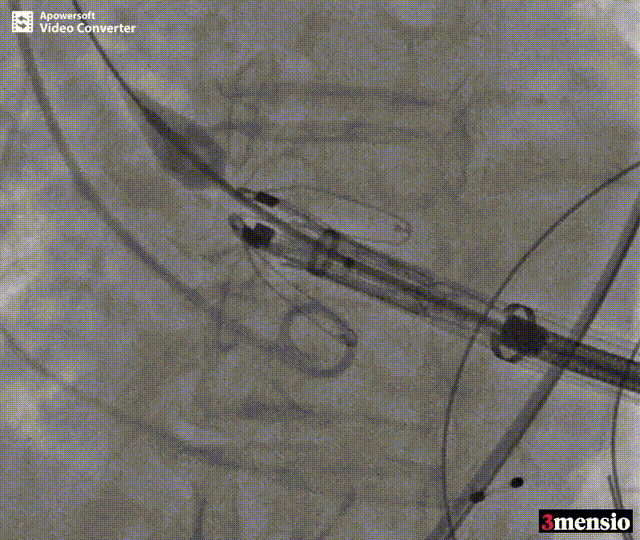

术中释放定位键后DSA影像图

术中瓣膜释放过程

患者全麻后,于左侧心尖3-4cm处进行微创手术切口。在DSA及超声引导下,输送Ken-Valve瓣膜系统进入左心室,边调弯边推送,使得瓣膜在术中始终保持较好的同轴性,从送入输送器到瓣膜释放不足十分钟。术后即刻患者反流消失,于外科杂交手术室拔除气管插管,次日即由ICU转入普通病房。